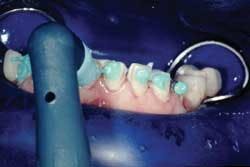

The veneers were tried in individually to ensure proper seating and marginal adaptation (Fig. 3).

Then, all at once with a water-soluble, try in paste (Prevue Yellow Red Light, in this case) to verify the shade and check the interproximal contacts (Fig. 4).

A Vivastick (Ivoclar Vivadent) often is used to transport mandibular veneers into place (Fig. 5).

Check the interproximal contacts of each veneer with either a thin strip of Accufilmor liquid AccufilmIV (Parkell). If the contacts are slightly tight, you will have an improper seating of the veneers and even potential for fracture of the porcelain trying to seat the veneer in place. This is the main reason I feel more comfortable seating only two veneers at a time. With this particular case, the color was predetermined from the maxillary porcelain. A shade match with try-in gels usually is done without the rubber dam in place.